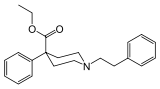

Others

Structures

| Other phenylpiperidines | |||

|---|---|---|---|

Alvimopan Alvimopan |

Loperamide Loperamide |

LS-115509 LS-115509 |

Picenadol Picenadol |